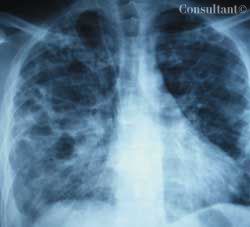

HIV AIDS